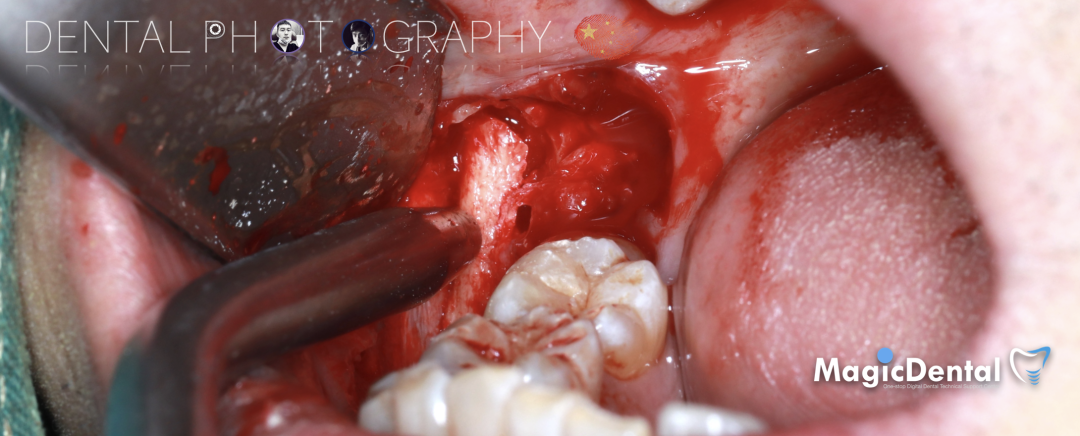

治疗计划:水平骨增量,拔除四区近中阻生智齿,下颌升支外斜线处取块状骨,移植骨块至受区(22唇侧),种植修复22缺失牙。

骨块细节

切开翻瓣,彻底暴露术区,试戴骨块。

调整骨块外形,适配受植区域,打开骨髓腔。

预备固位钉洞,固定骨块

骨膜减张,放置骨粉,放置骨块,钛钉固定骨块。

固定骨片,修整骨块边缘,继续放置骨粉覆盖骨块及受植区,放置骨膜,严密缝合创口。